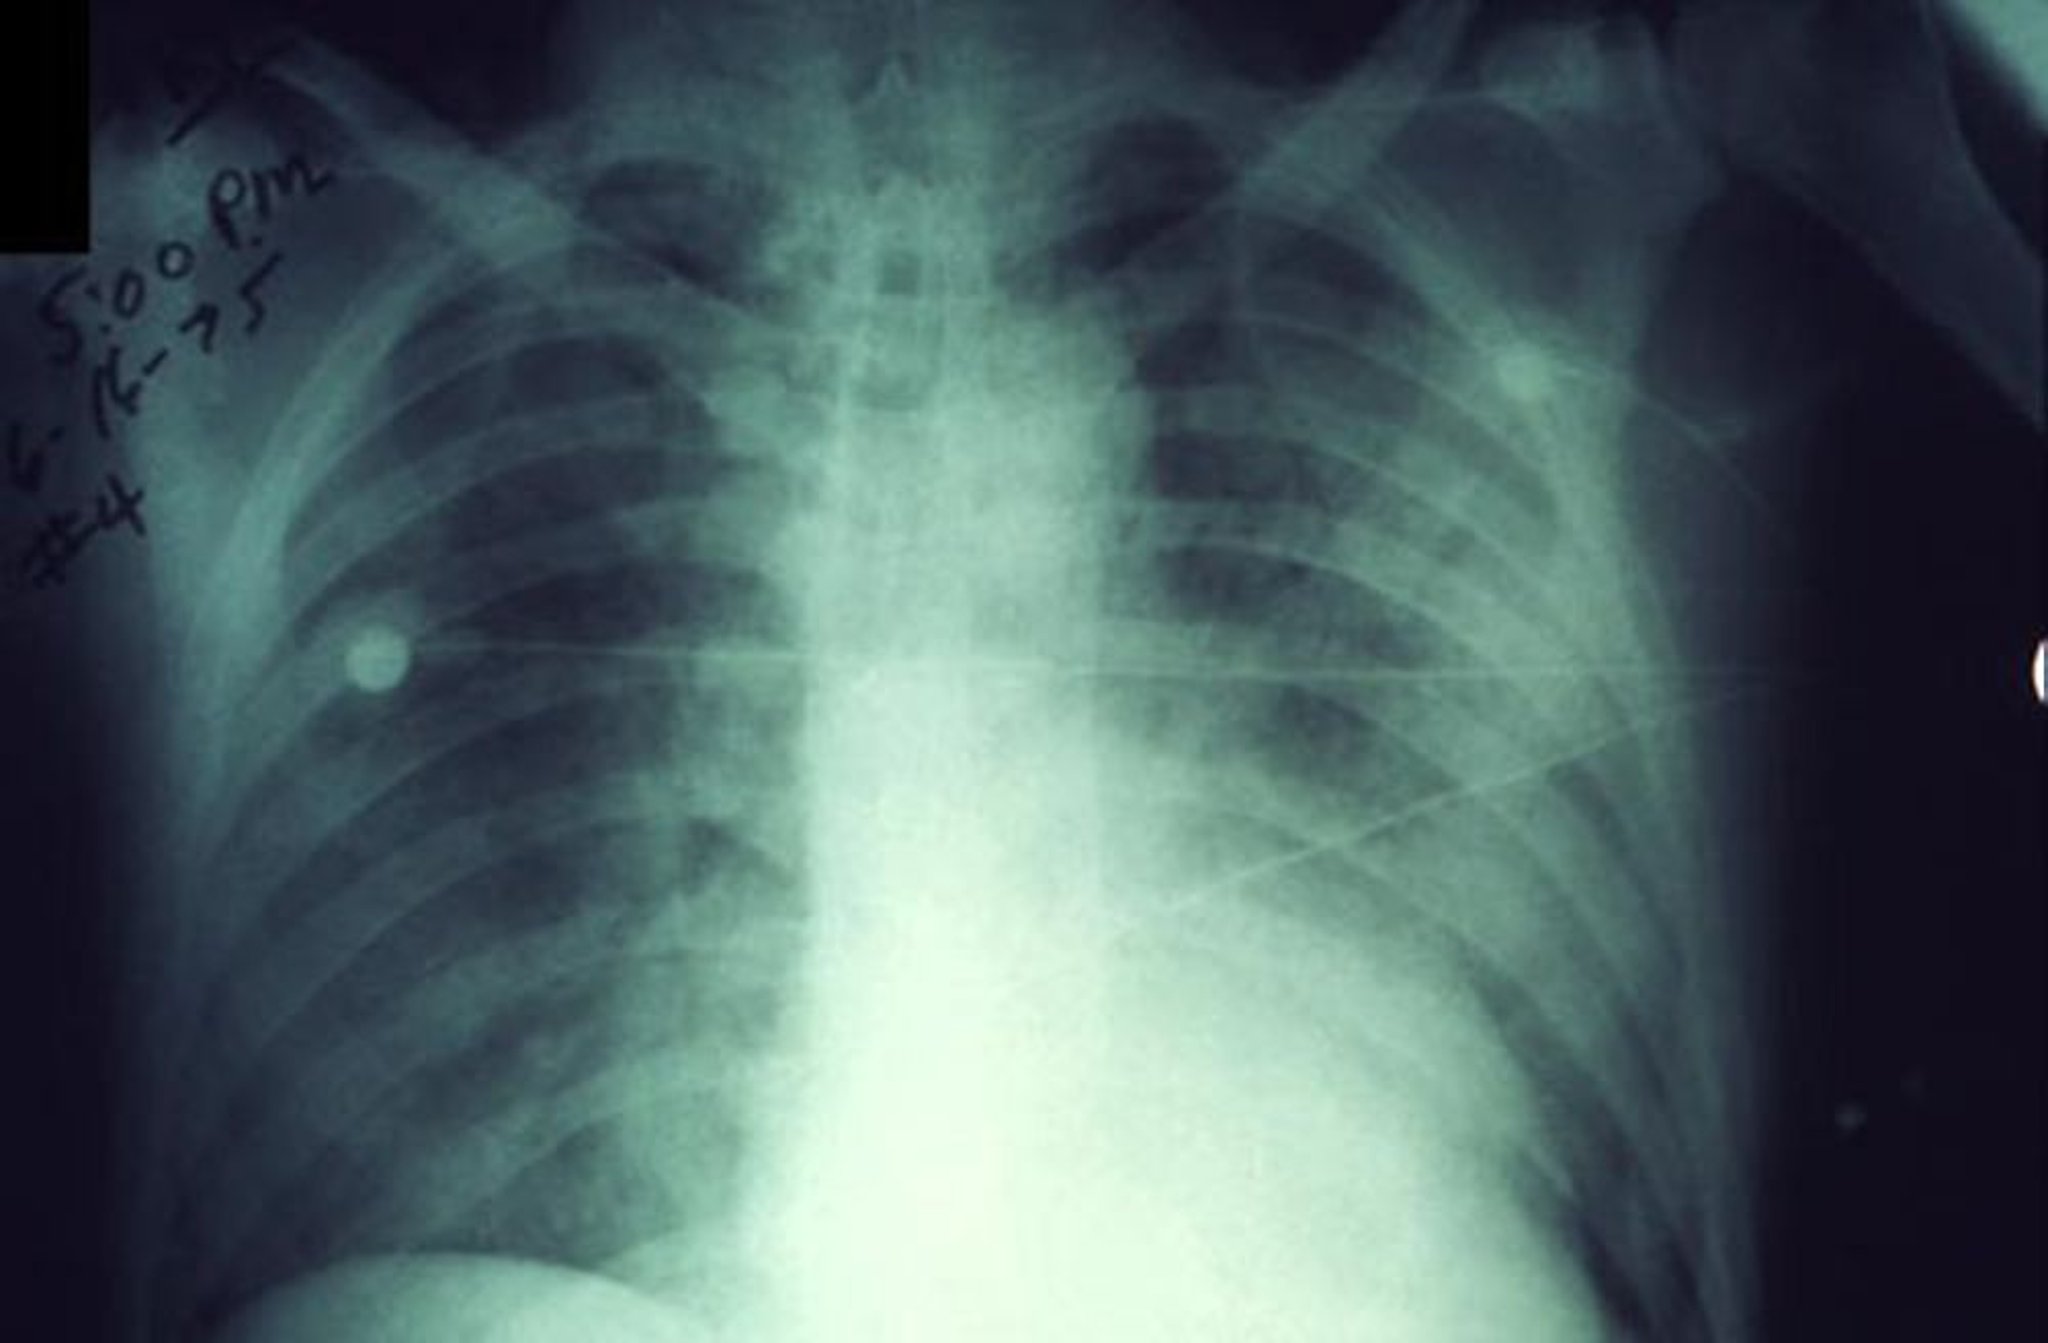

На данном рентгеновском снимке грудной клетки показаны быстро увеличивающиеся инфильтраты при легочной чуме.

CDC/Dr. Jack Poland